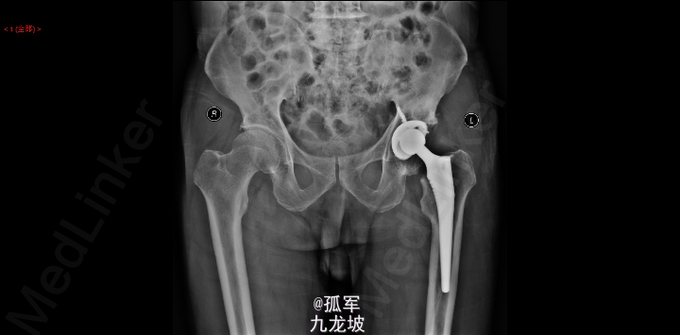

1.左侧Perthes病;2.左髋关节发育不良伴重度骨关节炎?3.腰椎间盘突出症 左侧人工全髋关节置换术 Link公司的TOP+LCU+陶瓷头